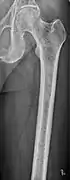

The diagnostic examination of a person with suspected multiple myeloma typically includes a skeletal survey. This is a series of X-rays of the skull, axial skeleton, and proximal long bones. Myeloma activity sometimes appears as "lytic lesions" (with local disappearance of normal bone due to resorption) or as "punched-out lesions" on the skull X-ray ("raindrop skull"). Lesions may also be sclerotic, which is seen as radiodense.[70] Overall, the radiodensity of myeloma is between −30 and 120 Hounsfield units (HU).[71] Magnetic resonance imaging is more sensitive than simple X-rays in the detection of lytic lesions, and may supersede a skeletal survey, especially when vertebral disease is suspected. Occasionally, a CT scan is performed to measure the size of soft-tissue plasmacytomas. Nuclear Medicine Bone scans are typically not of any additional value in the workup of people with myeloma (no new bone formation; lytic lesions not well visualized on nuclear bone scan).

- Multiple myeloma in the upper arm

- Femur with multiple myeloma lesions

- Same femur before myeloma lesions for comparison